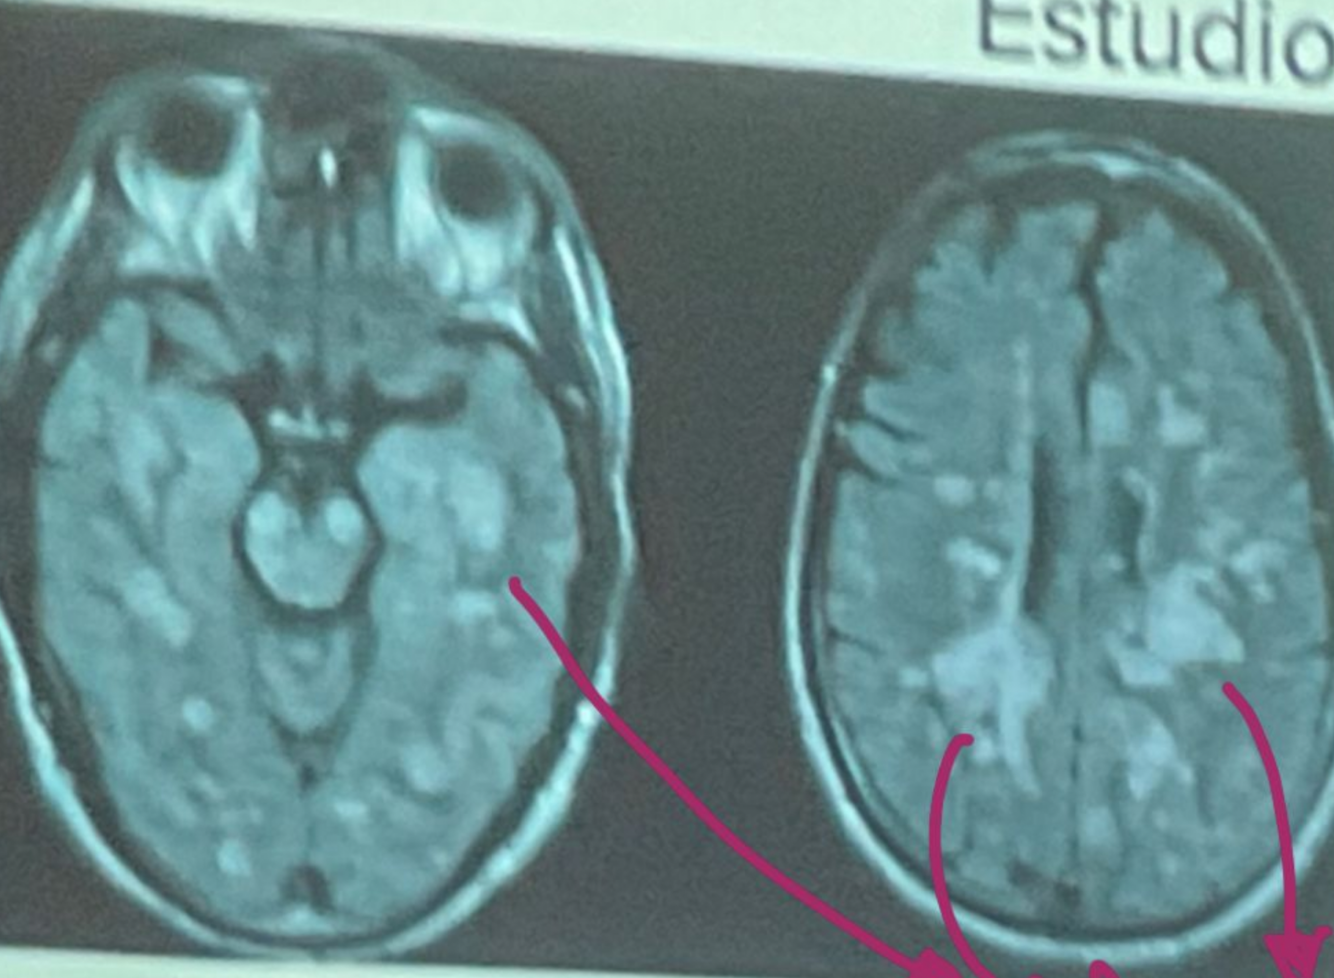

Q

Esta resonancia corresponde a ADEM/EM

A

ADEM

How well did you know this?